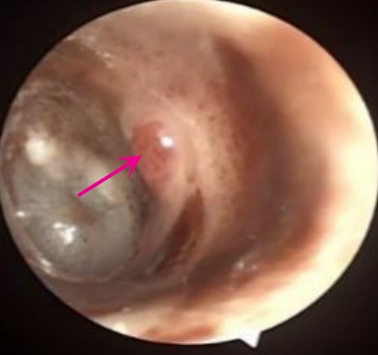

摘要:目的 探讨耳内镜下耳屏软骨-软骨膜鼓膜修补术后的短期疗效。方法 回顾性分析2019年9月-2022年8月该院收治的78例鼓膜穿孔患者的临床资料,患者均采用耳内镜下鼓膜修补术。术后随访3个月,观察鼓膜形态和穿孔愈合情况,记录内镜图像、干耳时间、术前术后听力及耳鸣情况,以及外耳道狭窄等并发症的发生率。结果 术后3个月,鼓膜穿孔愈合率为97.44%(76/78),愈合良好,平均气导听阈较术前明显改善,气骨导间距较术前明显缩小,耳鸣较术前明显改善,差异均有统计学意义(P<0.05)。干耳时间为(4.21±1.12)周。术后出现肉芽5例,再穿孔2例,真菌感染2例,术腔感染、耳屏感染、外耳道狭窄和切口瘢痕各1例,所有患者术后均未发生面神经麻痹和感音神经性聋等严重并发症。结论 耳内镜下耳屏软骨-软骨膜鼓膜修补术是一种安全、有效的手术方法。根据术后愈合规律、内镜下鼓膜和外耳道形态特征,可为鼓膜修补术后正常中耳转归和并发症的诊疗,提供临床参考。